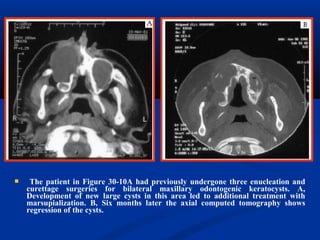

 The patient in Figure 30-10A had previously undergone three enucleation and

curettage surgeries for bilateral maxillary odontogenic keratocysts. A,

Development of new large cysts in this area led to additional treatment with

marsupialization. B, Six months later the axial computed tomography shows

regression of the cysts.